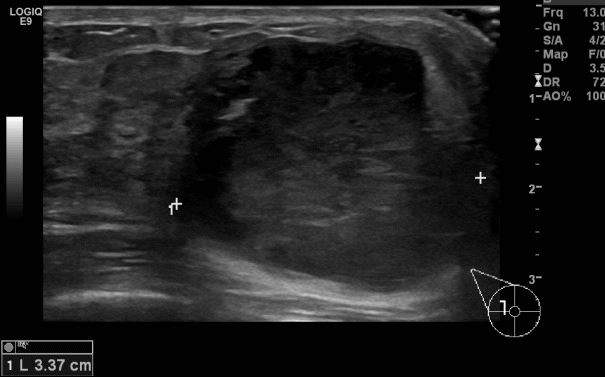

우측 만져지는 멍우리로 내원하신 20대 여성분으로 우측 12시 방향 4cm 이상 크기의

멍울 중심핵생검 시행하여 우측 침윤성 유관암 진단 되었습니다.